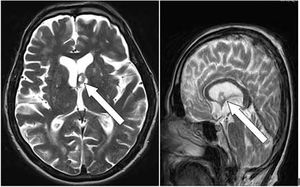

Case History: 45-year-old female with complaint of occasional headache for three years, had normal neurological and systemic exams.